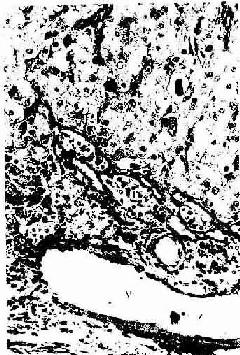

图17-9 人卵巢黄体细胞 HE×400

G粒黄体细胞 T膜黄体细胞V血管

成熟卵泡排卵后,残留在卵巢内的卵泡壁塌陷,卵泡膜内的血管和结缔组织伸入颗粒层。在LH的作用下。卵泡壁的细胞体积增大,分化为一个体积很大并富含血管的内分泌细胞团,新鲜时呈黄色,称为黄体(corpus luteum)(图17-1)。颗粒细胞分化为粒黄体细胞(granular lutein cell),膜细胞分化为膜黄体细胞(theca lutein cell)。粒黄体细胞较大,呈多角形,染色较浅,数量多;膜黄体细胞较小,圆形或多角形,染色较深,数量少,分布于黄体的周边部(图17-9)。这两种细胞具有分泌类固醇激素细胞的结构特征,细胞内有丰富的滑面内质网和管状嵴的线粒体,还有脂滴和黄色脂色素。黄体的主要功能是分泌孕激素和一些雌激素,前者由粒黄体细胞分泌,后者主要由两种细胞协同分泌。